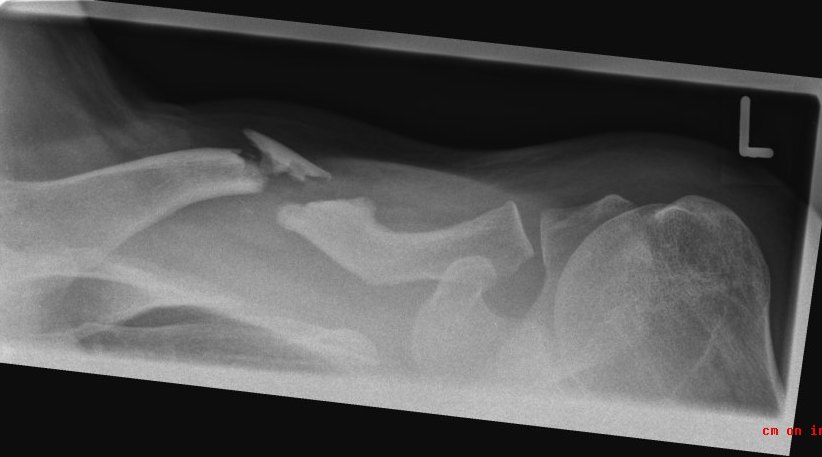

Siehe Bild. Die Chirurgen haben da etwas gepuzzelt. Ging halt nicht anders, wegen Splitter und Fehlstellung. Wäre zwar ohne OP irgendwie zusammengewachsen, dann aber definitiv schief. Und dann eben noch die Problematik, dass es sehr lange ruhiggestellt werden müsste und das Schulter sehr schnell versteift. Und da ich (hoffentlich) noch einige Jahrzehnte zu leben habe, wollte ich nicht dauerhafte Probleme haben (Verkürzung, Schmerzen, Bewegungseinschränkungen etc). Jetzt nach 3 Wochen darf ich auch schon über 90° nur eben nicht belasten.